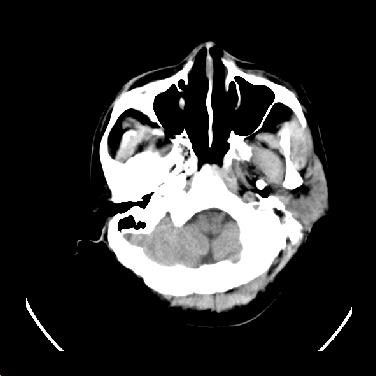

标题: CT16999:男,45岁,左侧肢体乏力1周。请会诊 [打印本页]

男,45岁,左侧肢体乏力1周。ex:胸片示:两肺团块状、斑片状密度增高影,其内可见小空洞。支纤镜、经皮肺穿示:干酪样物。

结合病史考虑结核性脑炎脑膜炎,伴脑脓肿形成

考虑结核性脑炎脑膜炎,伴脑脓肿形成。